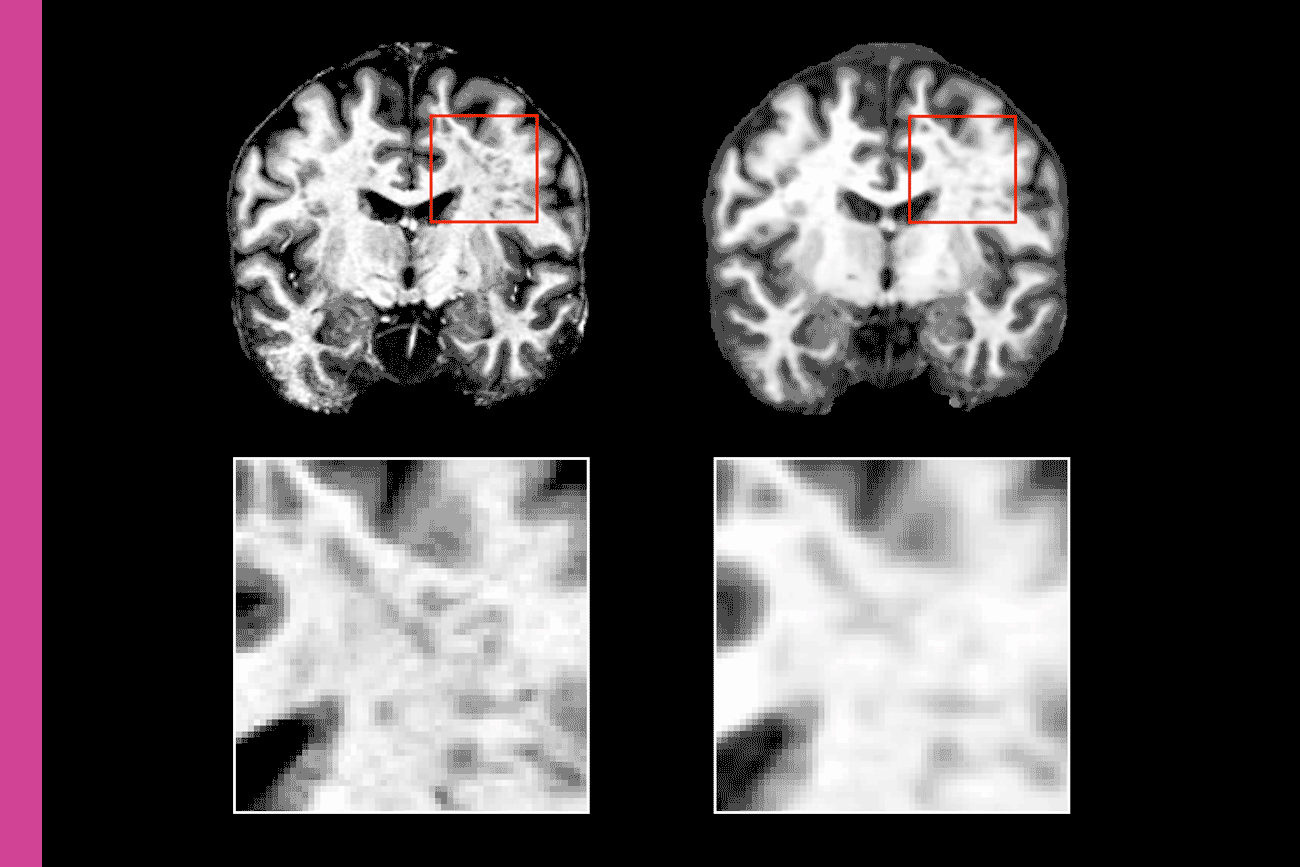

In a study published in May 2025, Milch investigated whether an AI radiology tool called Transpara could detect breast cancers that human radiologist missed while reading routine screening mammograms. Studying nearly 185,000 mammograms conducted between 2010 and 2019, her team found that Transpara spotted about 30 percent of these so-called interval cancers.

“It's encouraging to see that if that radiologist were in that situation again, and they had the AI support tool flagging that spot, that cancer may have been caught five, six, eight months earlier, when it’s easier to treat,” Milch says.

Now Milch is co-leading a larger study in which over 400,000 mammograms will be randomly assigned to be read either by a radiologist on their own or with assistance from Transpara. The PRISM trial, also led by Milch’s UCLA Health Jonsson Comprehensive Cancer Center colleague Dr. Joann Elmore, Dr. Diana Miglioretti at UC Davis and Dr. Christoph Lee at the University of Wisconsin—Madison, is the nation’s largest-ever randomized prospective trial of AI in breast cancer screening. “We’ll be looking to see if patient outcomes are actually better when the radiologist had AI helping them,” Milch says. “We want to make sure that these tools are safe and effective before they're widely bought up and put into clinical use.”